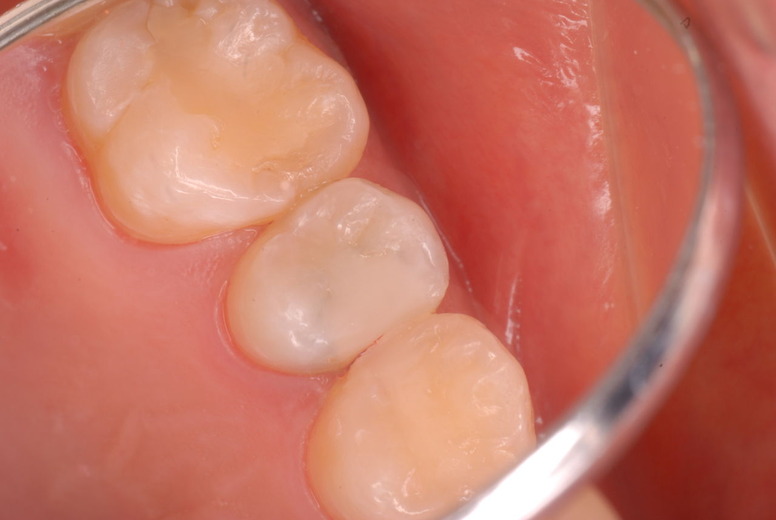

歯周病になっていましたが、少し色が黄色くなっているだけで比較的綺麗な歯の状態です。

平成9年来院神経を取り、同時に歯周病の話をしてそのまま来なくなっていたかたですが、たまたま一部欠けてきました。それで来院。

平成24年一部欠けて来院

15年前と同じように詰めて終了。磨き方はまあまあでした。でも問題少ないでしょう。![ea7f9628-s[1]](https://livedoor.blogimg.jp/netdental/imgs/c/2/c2ef91be.jpg)

虫歯という病気を完全に治し、神経の処置で神経の病気を治し、ブラシの使い方をマスターすれば歯やお口の中は問題を起こしにくいのです。何かを被せることは注意が必要ですし、歯を傷つける訳ですからブラシの使い方をマスターしてから被せないと危ないのです。